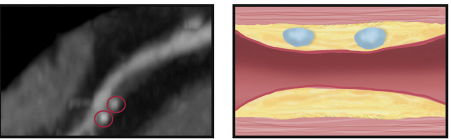

Plaques à Risque

Remodellage positif

Core lipidique <30 HU

Napkin ring sign

Spotty calcifications